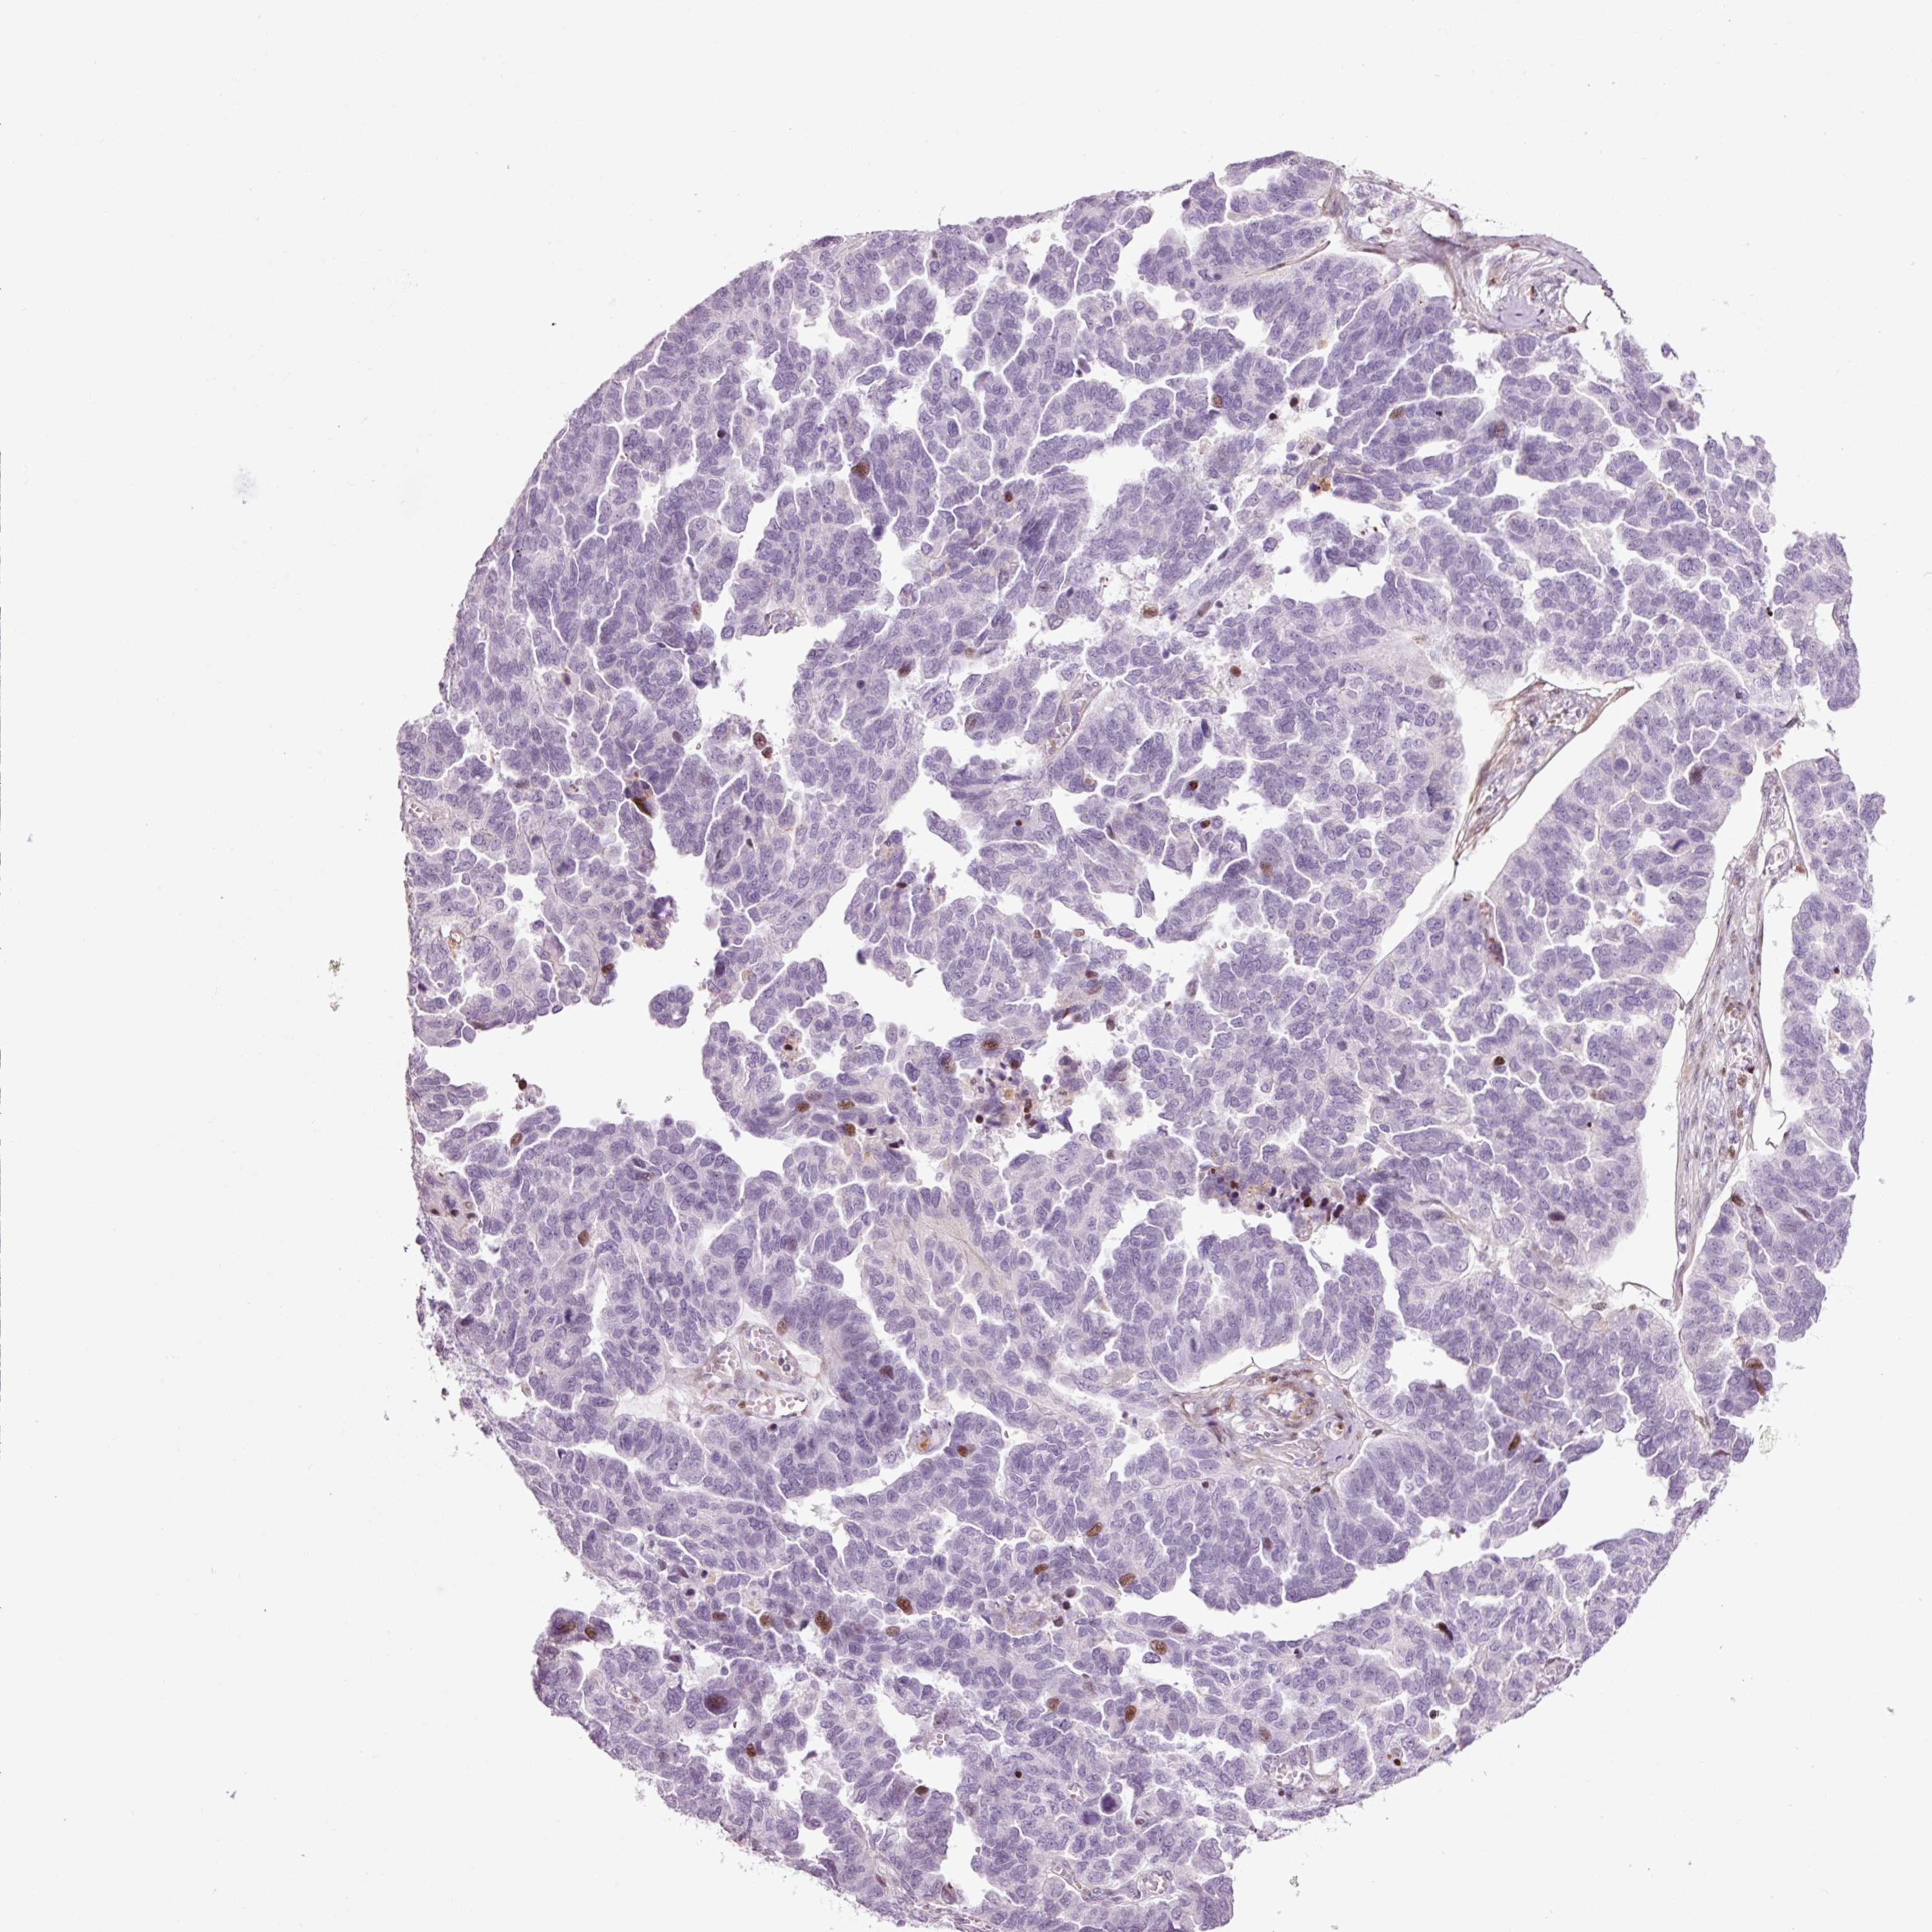

OVARIAN CANCER - Protein expressioni

A mouse-over function shows sample information and annotation data. Click on an image to view it in a full screen mode. Samples can be filtered based on level of antibody staining by selecting one or several of the following categories: high, medium, low and not detected. The assay and annotation is described here.

Note that samples used for immunohistochemistry by the Human Protein Atlas do not correspond to samples in the TCGA dataset.

Antibody stainingi

Antibody staining in the annotated cell types in the current human tissue is reported as not detected, low, medium, or high, based on conventional immunohistochemistry profiling in selected tissues. This score is based on the combination of the staining intensity and fraction of stained cells.

Each image is clickable and will lead to virtual microscopy that enables deeper exploration of all samples and also displays staining intensity scores, fraction scores and subcellular localization as well as patient and tissue information for each sample.

HPA046346

Staining

High

Medium

Low

Not detected

Intensity

Strong

Moderate

Weak

Negative

Quantity

>75%

75%-25%

<25%

None

Location

Nuclear

Cytoplasmic/membranous

Cytoplasmic/membranous,nuclear

Carcinoma, NOS